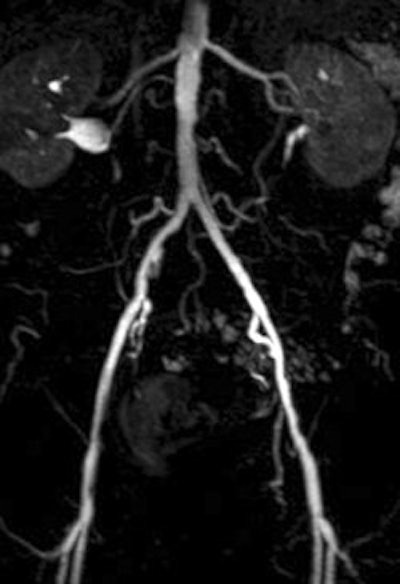

Of the nine patients, the majority had arterial occlusive disease of the iliac axis. The patients underwent angiography and angioplasty with a 6-French introducer left in the common femoral artery.

For the patients, maximum intensity projections (MIPs) were calculated from the contrast-enhanced images. Image quality for evaluating the renal arteries was graded on four-point scale (1 = excellent, 4 = poor). In the phantom, intraluminal signal intensity was measured distal to the tip of the catheter along the tube.

| A 78-year-old man with peripheral arterial occlusive disease. Lumbar arteries are evident with both MRI acquisition techniques. Iliac axis has good runoff on both sides after percutaneous transluminal angioplasty (above). Anteroposterior maximum intensity projection 3D fast low-angle shot (FLASH) intra-arterial MR aortogram obtained with standard technique (below). |

According to the results of the patient study, both techniques were well tolerated and had no side effects. In addition, the diagnostic value of GRAPPA MRA was given an average grade of 2.2 compared to 2.0 for FLASH MRA. Using the parallel acquisition technique, the CNR ranged from 32.0 in the renal arteries to 125.5 in the aorta.